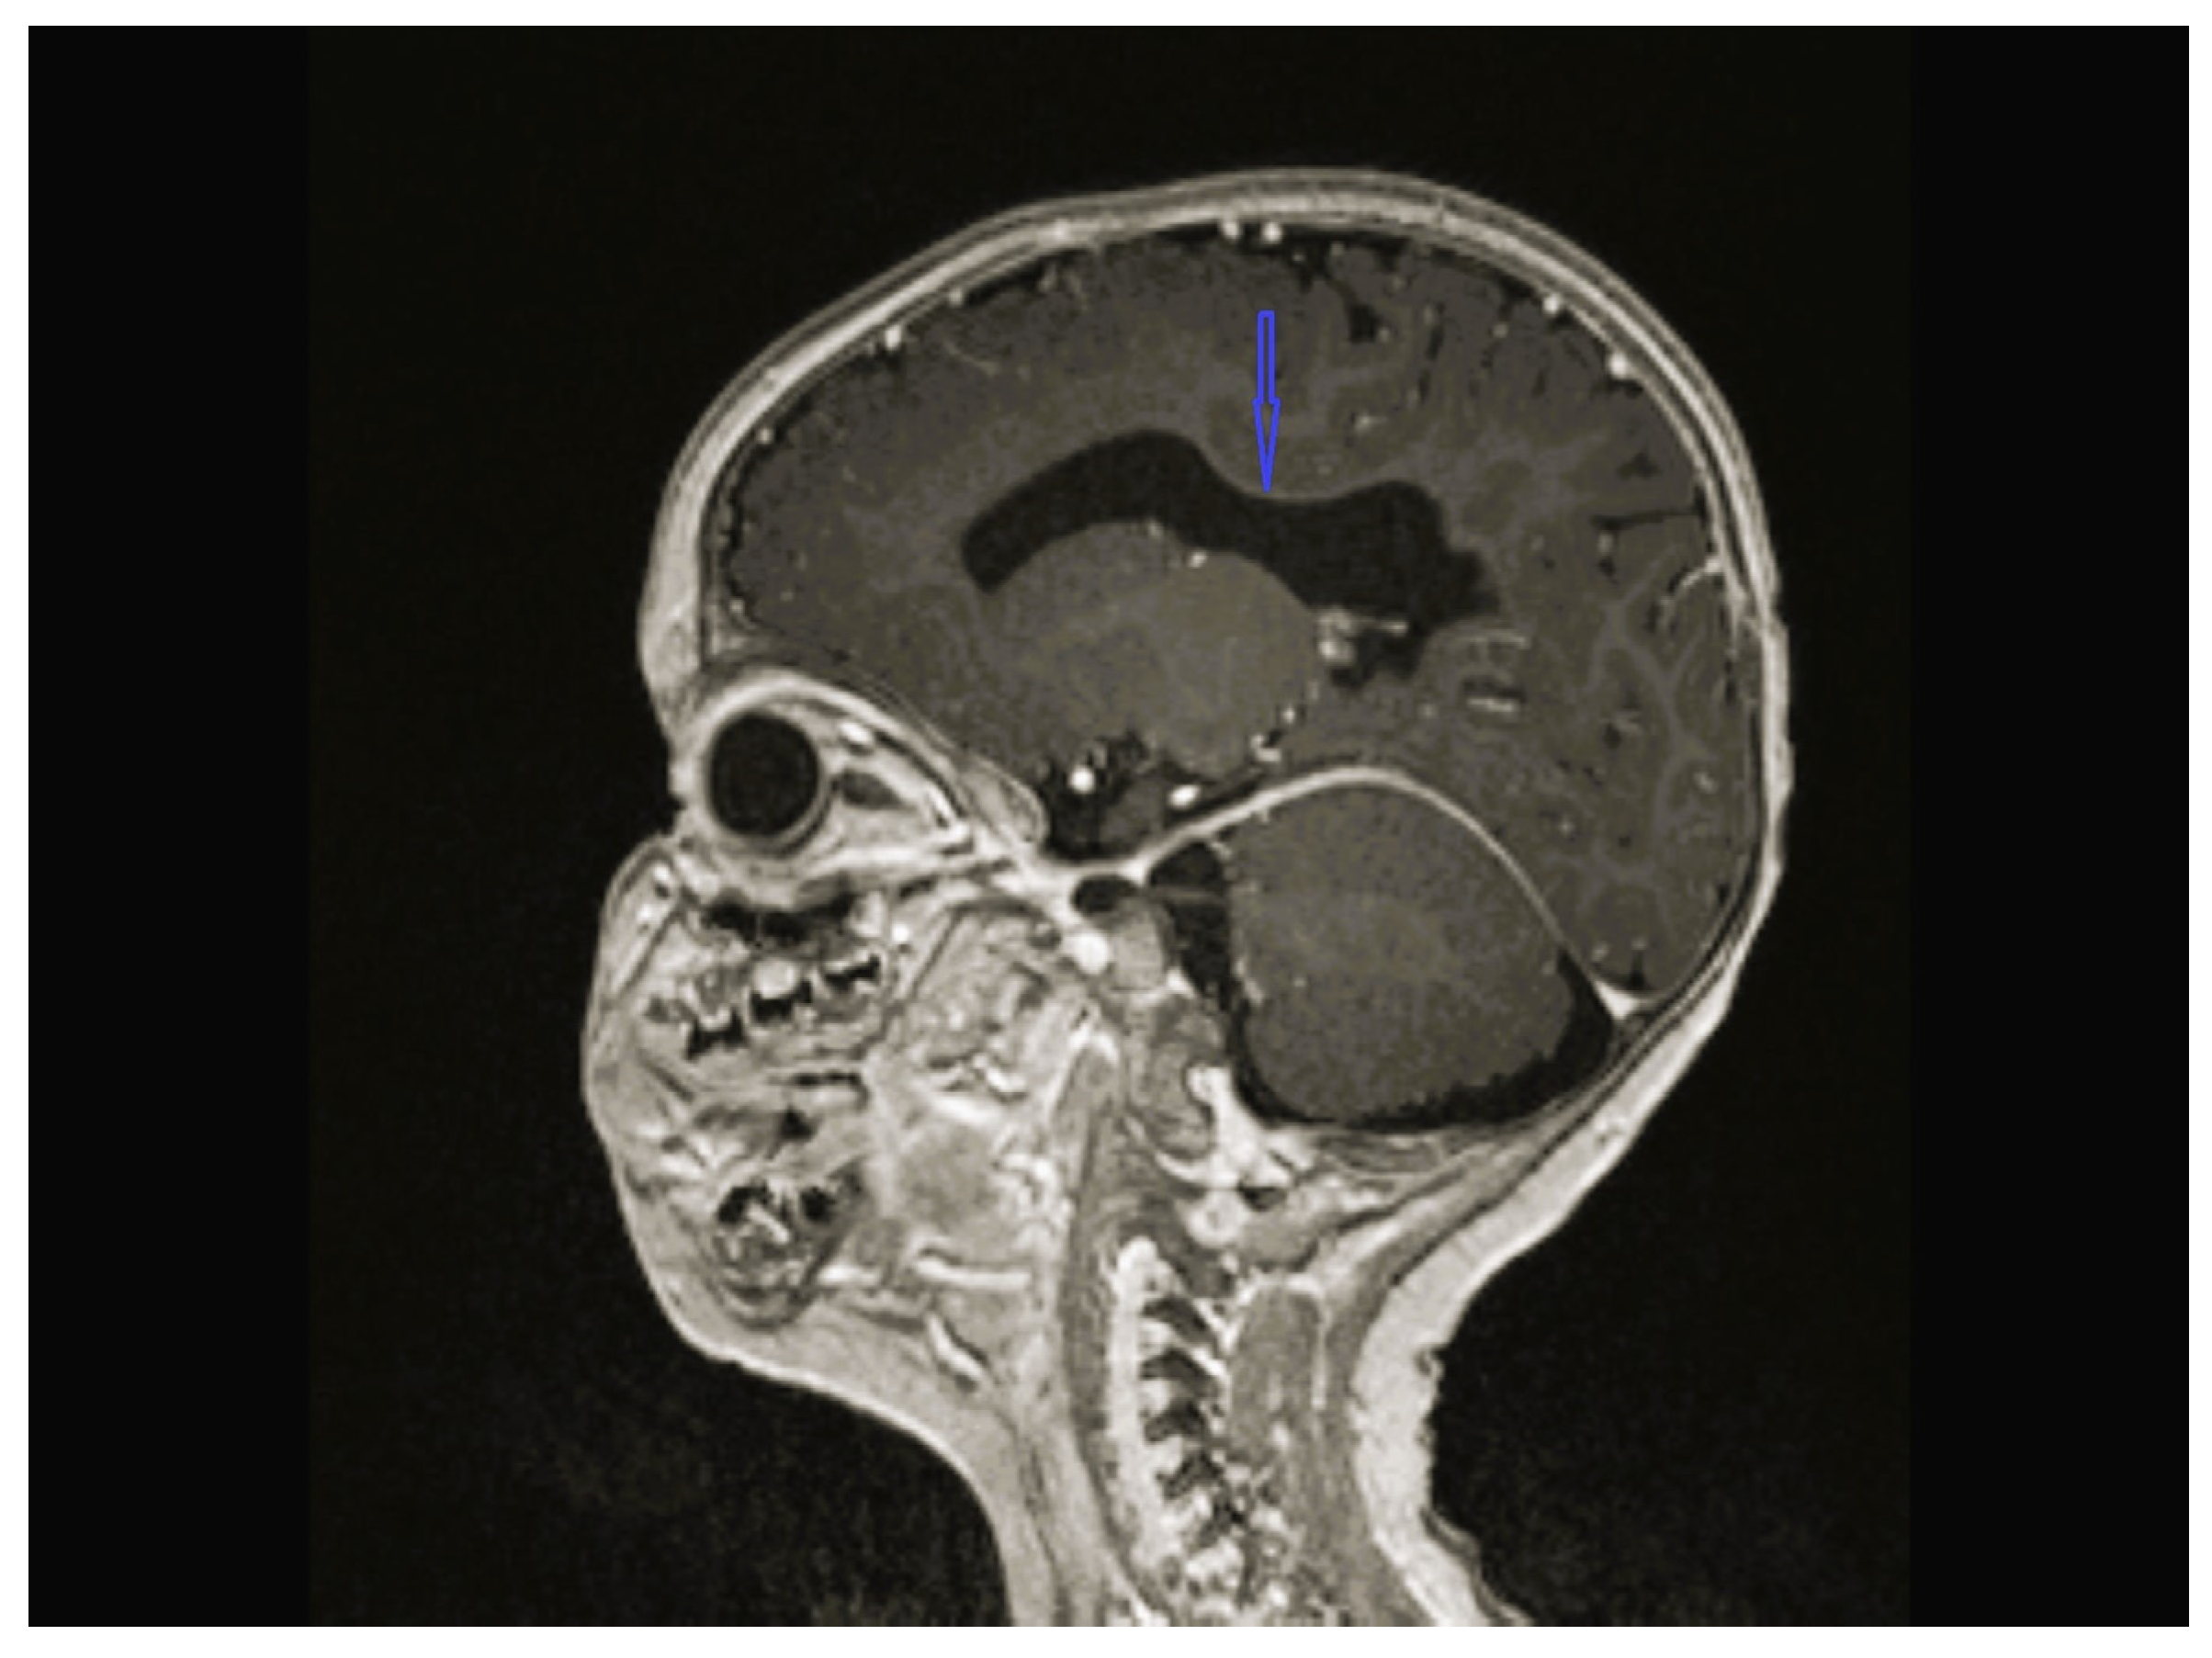

| 1 | - | - | - | Cerebellar hypoplasia, vermis dysplasia and corpus callosum (CC) hypoplasia | Normal | SPG11 c.6730C>T heterozygote (p.L2244F) | Physical therapy |